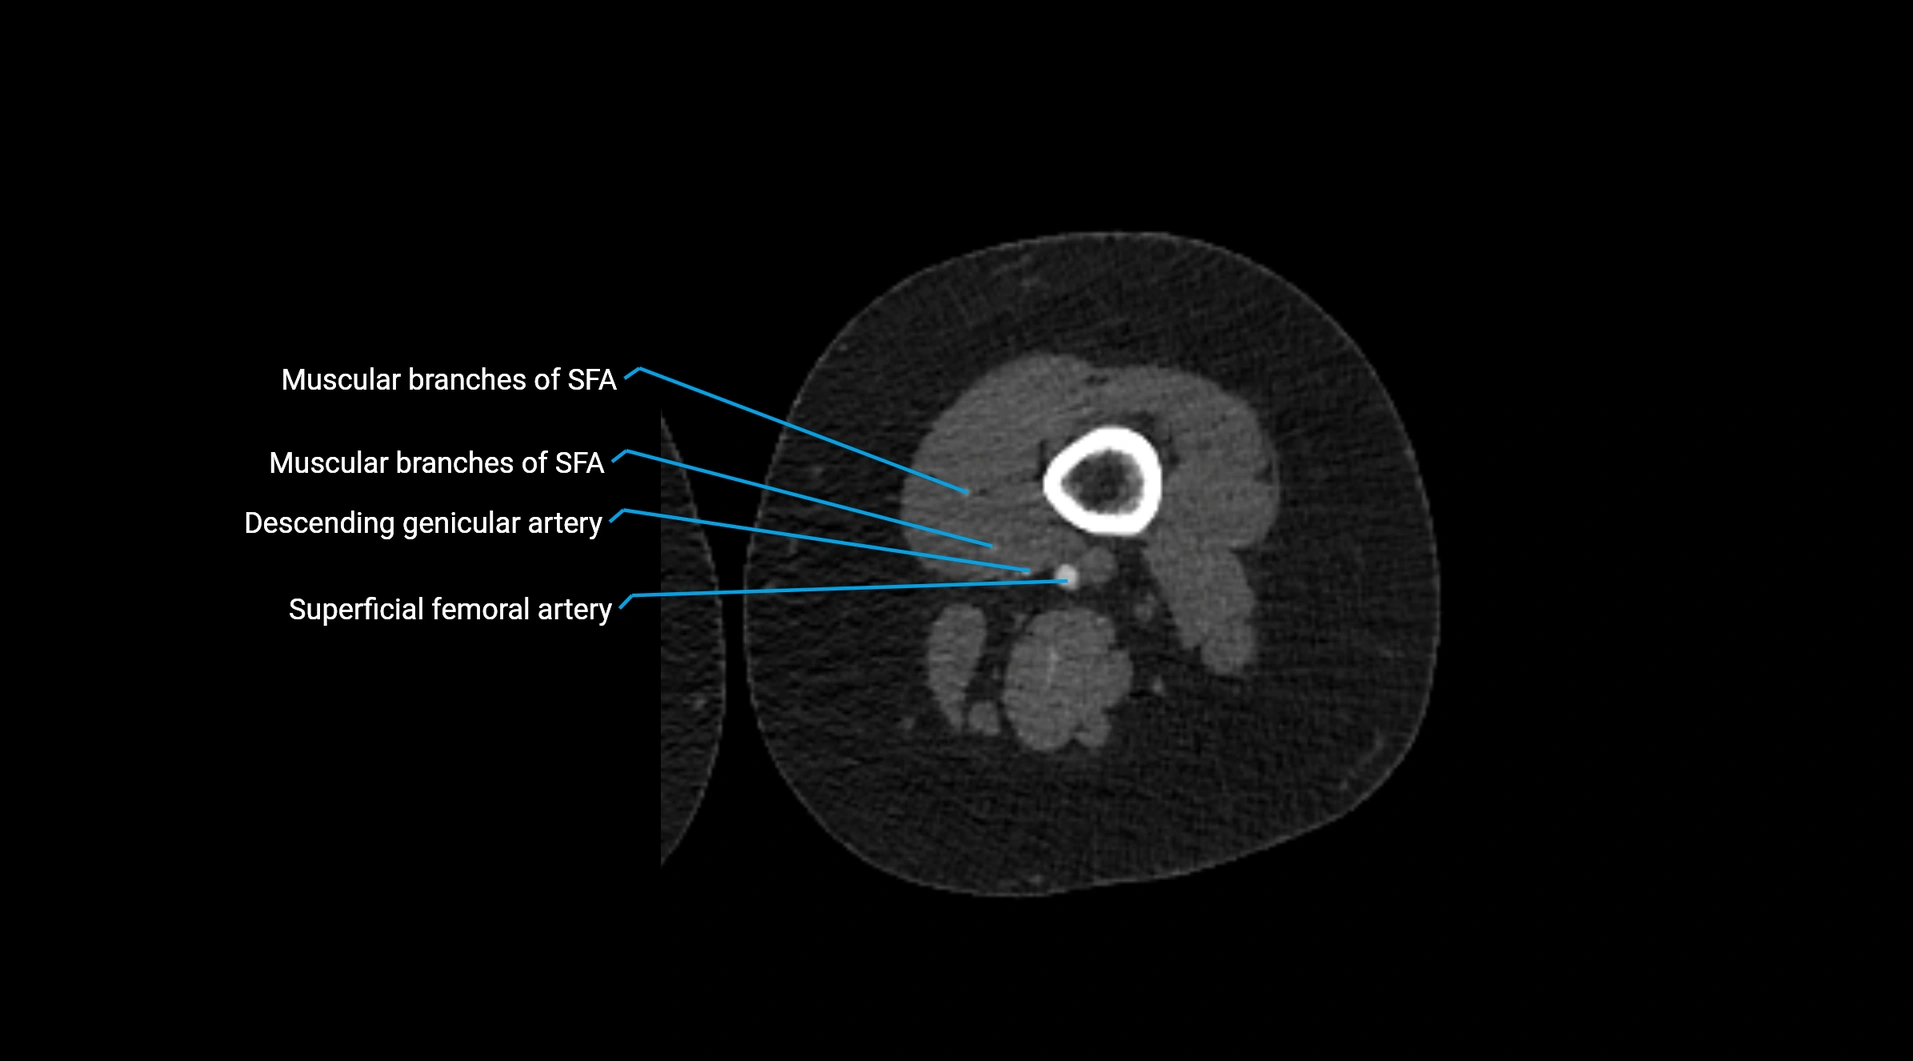

CT Appearance

Non-contrast CT:

• Appears as a tubular soft tissue structure anterior to vertebral bodies

• Calcified atherosclerotic plaques appear as hyperdense foci along the wall

• Useful for screening abdominal aortic aneurysm (AAA) size and mural calcification

Contrast-enhanced CT (CTA):

• Gold standard for abdominal aortic imaging

• Provides excellent detail of lumen, wall, aneurysm, thrombus, and branch vessels

• Multiplanar and 3D reconstructions help in aneurysm measurement, stent graft planning, and dissection evaluation

• Detects acute rupture, traumatic injury, or occlusion with high sensitivity